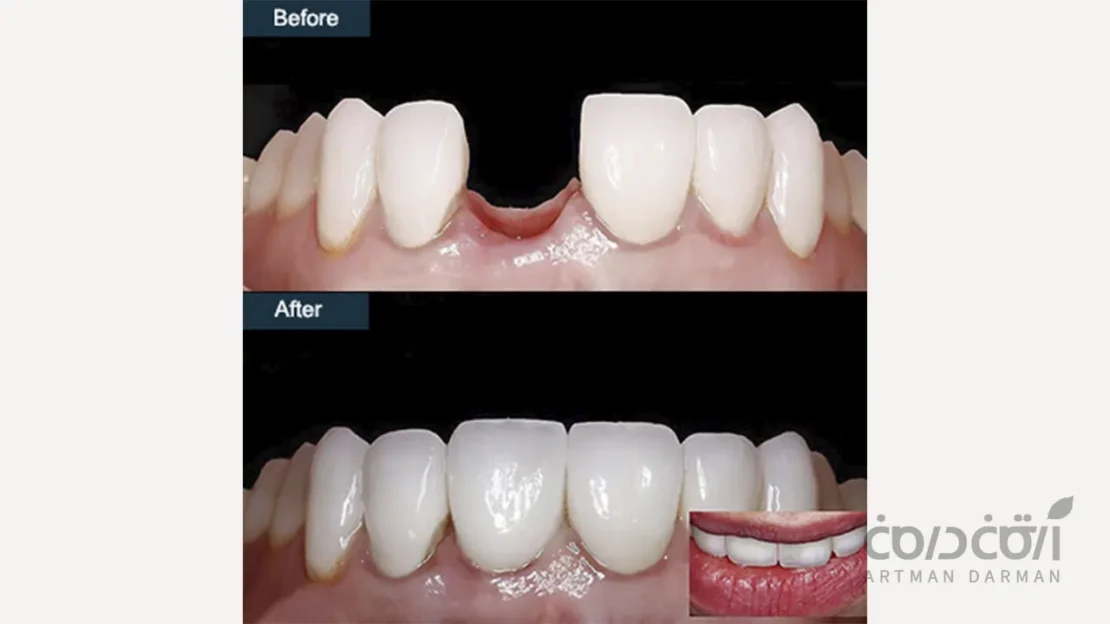

زیبایی شناسی طبیعی و غیرقابل تشخیص

علم مواد و هنر دندانپزشکی در سال های اخیر به نقطه ای رسیدهاند که می توان یک روکش ایمپلنت را به گونه ای ساخت که از دندان طبیعی مجاورش غیرقابل تشخیص باشد.

با استفاده از روکش های تمام سرامیک (مانند E.max یا زیرکونیا) و اباتمنت های سفارشی همرنگ دندان، می توانیم رنگ، شفافیت، شکل و بافت سطحی دندان طبیعی را با دقتی شگفت انگیز بازسازی کنیم. نحوه بیرون آمدن روکش از لثه نیز به گونه ای طراحی می شود که کاملاً طبیعی به نظر برسد. بنابراین در مقام مقایسه ایمپلنت با دندان واقعی از نظر ظاهری تقریبا چیزهای یکسانی می بینیم.